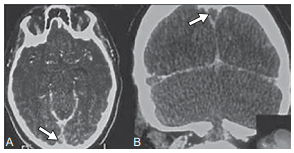

Mulher de 32 anos, previamente hígida, iniciou com cefaleia

intensa e progressiva há cinco dias, associada a visão turva

e episódios de vômito. No exame físico, apresenta papiledema bilateral e discreta hemiparesia direita. A tomografia

computadorizada de crânio com contraste encontra-se a

seguir.

Com base nesses achados, qual é o diagnóstico mais provável e sua opção terapêutica inicial.